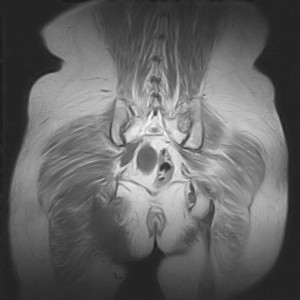

图像太差了 1、右侧臀肌旁脓肿? 建议增强 2、左侧股骨头坏死并半脱位

1、左侧股骨头坏死并髋关节半脱位;

2、右侧臀肌感染,(可能褥疮所致)